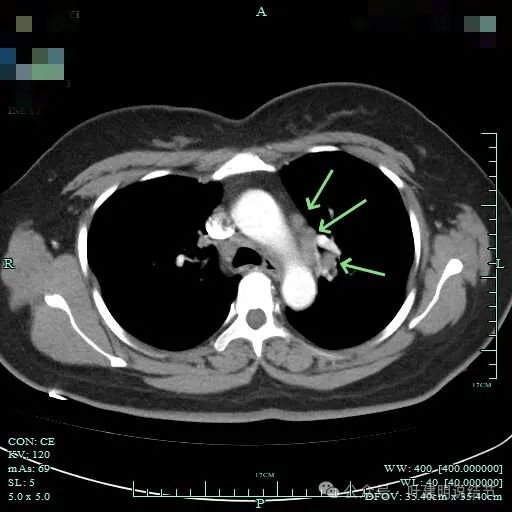

隆突下明显肿大淋巴结

左侧肺门与纵隔肿大淋巴结

左侧肺门处淋巴结肿大明显。

双侧肺门与纵隔明显肿大淋巴结。